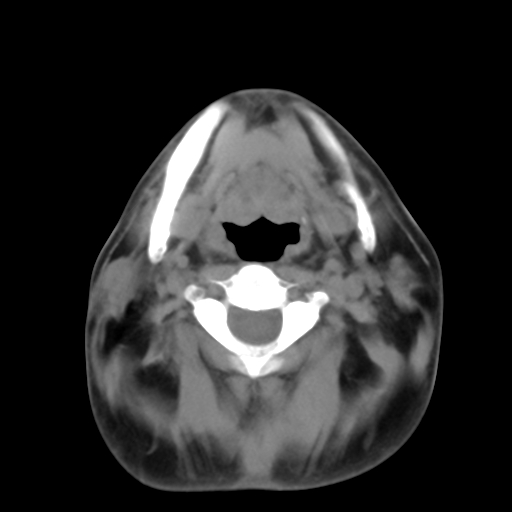

标题: CT24019:男,45岁,发现颈部肿物5个月。 [打印本页]

标题: CT24019:男,45岁,发现颈部肿物5个月。

男,45岁,发现颈部肿物5个月,彩超示:双侧颈部及下颌部软组织增厚。

考虑双侧颈项部良性对称性脂肪增多症。